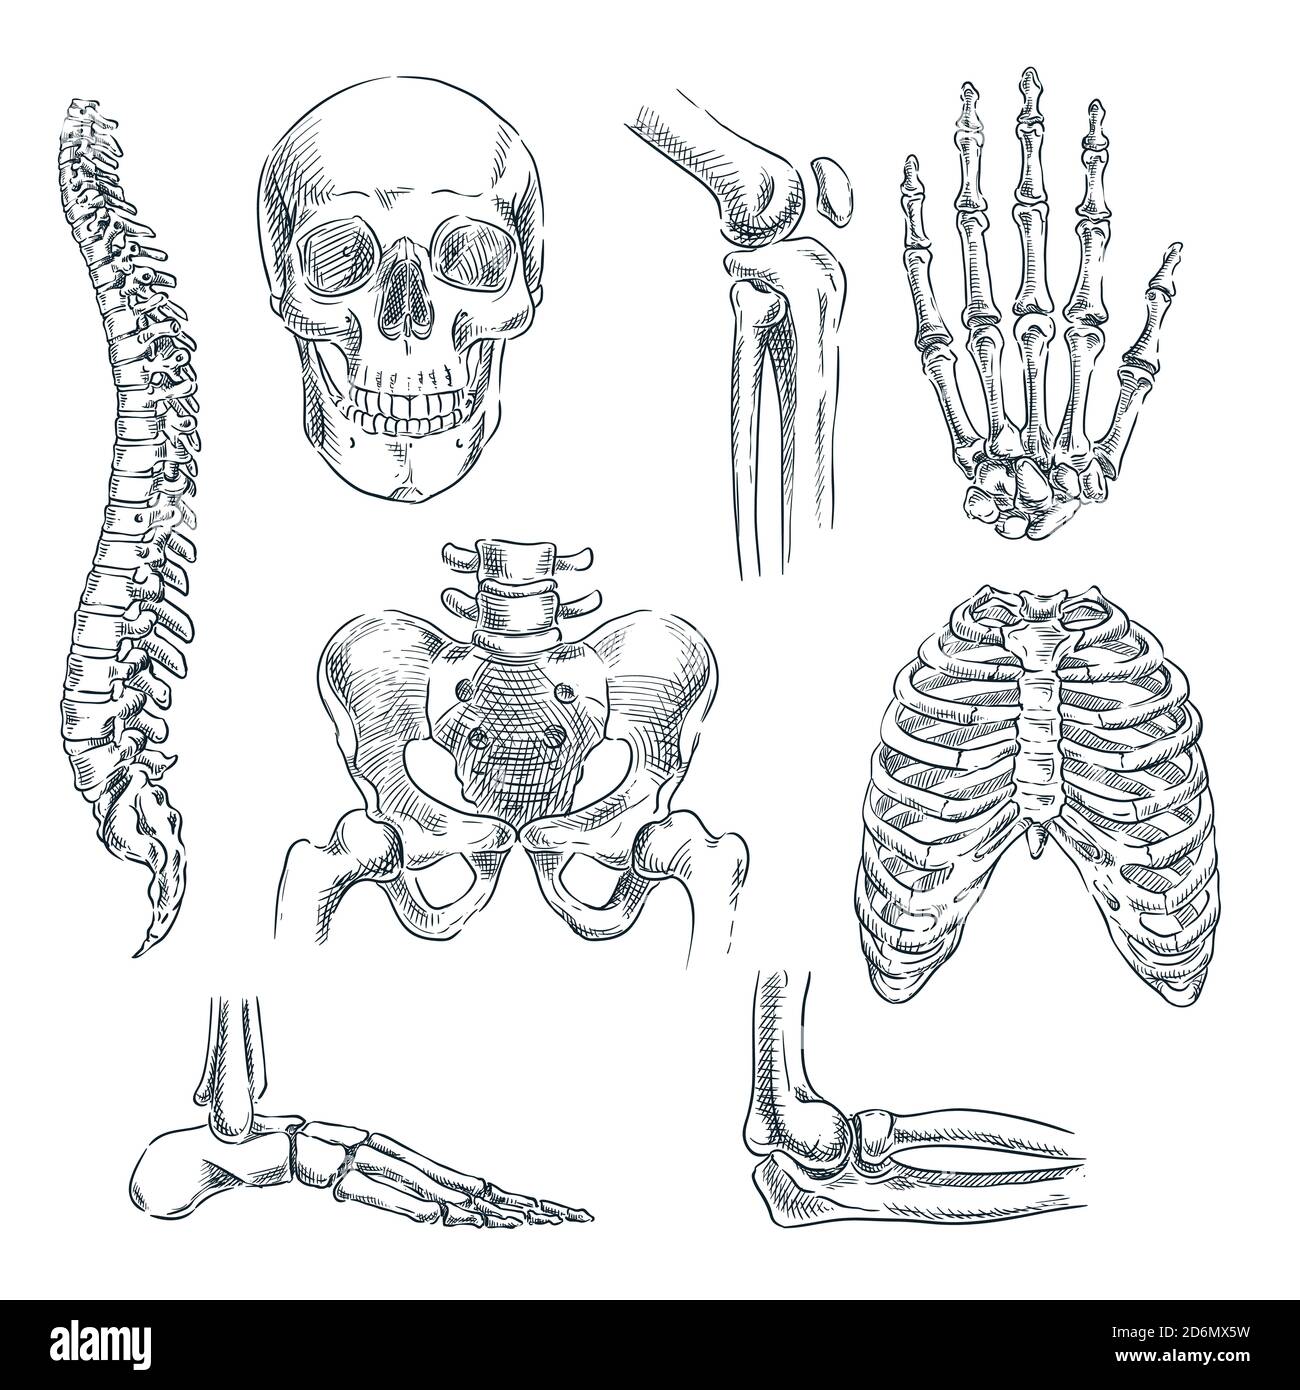

RF2D37MDD–Squelette humain. Parties du corps crâne os mains pied rachis anatomie détaillée réaliste illustration vectorielle

RF2D6MX5W–Squelette humain, os et articulations. Illustration isolée d'esquisse vectorielle. Jeu de symboles anatomiques pour les caniche dessinés à la main.